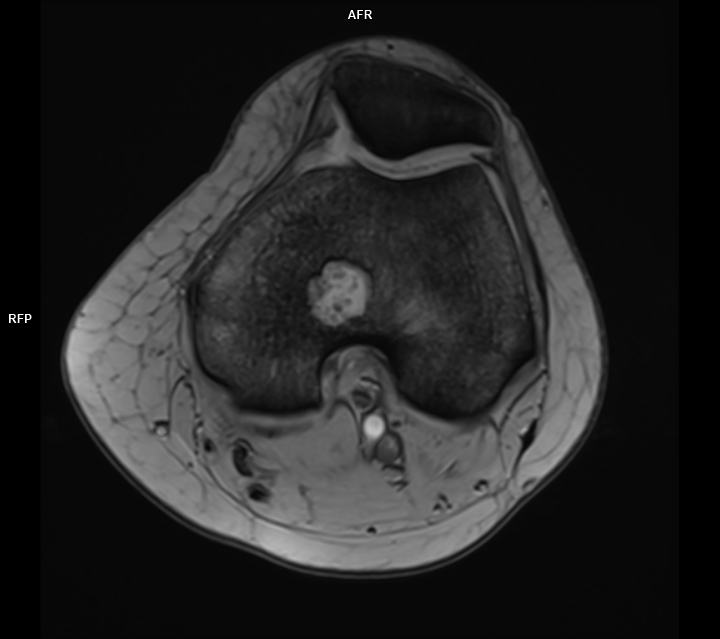

CAZ nr 44 Encondrom femural distal

Figura 3: achiziție în plan axial în ponderație PD cu saturația grăsimii

Discuție caz nr 44: Encondromul este o tumora benignă cu origine cartilaginoasă; cazul prezentat evidențiază o leziune net delimitată în hipersemnal PD, hiposemnal T1, fără restricție de difuzie, ce nu modifica semnalul țesutului osos de vecinătate si se dezvoltă de o parte şi de alta a cartilajului de creștere.